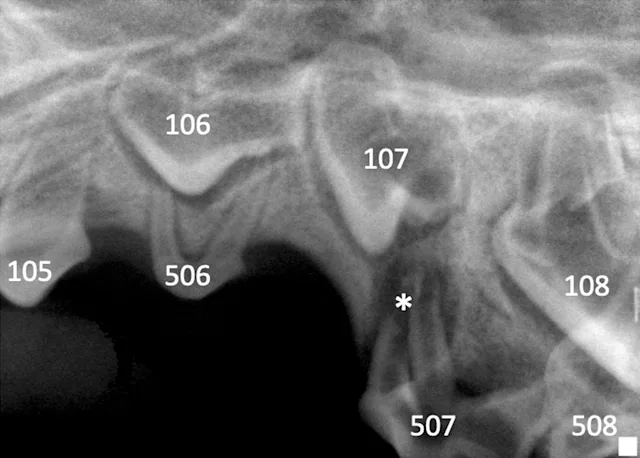

Dental radiography via a veterinary digital intraoral sensor and oral examination were performed with Uma under anesthesia. A slab fracture was seen on the palatal surface of 507 with pulpal exposure (Figure 2); a probe was easily inserted into the pulp cavity. No abnormalities were noted on the left side (Figure 3). Radiographs of the fractured tooth and its contralateral counterpart revealed a radiolucent area at the apexes of the mesial (ie, rostral, side of the tooth directed toward the first incisor) roots of 507.

Underlying developing adult teeth can complicate interpretation of dental radiographs.